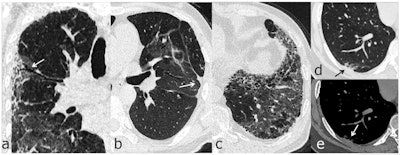

To address this knowledge gap, Han's group assessed pulmonary sequelae on six-month follow-up chest CT scans in 114 patients who survived severe COVID-19 (all patients underwent chest CT at symptom onset). Lung changes included opacification, consolidation, reticulation, and fibrotic changes.

The investigators found that 35% of the study participants (40 of 114) went on to develop lung changes within six months. Patients with the following factors at disease onset were at higher risk of manifesting signs of lung damage at six-month follow-up: